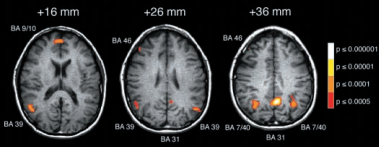

조슈아 그린 등은 이 두 가지 문제의 답을 결정할 때 뇌의 어느 영역이 활성화되는지를 연구했습니다. 같은 딜레마를 담고 있는 문제이더라도 인간과의 접촉이 없이 단지 조종간을 당기느냐 마느냐를 결정하는 첫 번째 질문의 경우 뇌에서 추상적 문제 해결에 관여하는 뇌의 영역, 즉 우내측 이마이랑, 양측 두정엽이 활성화되었고, 직접 눈앞의 인간을 밀어야 하는 두 번째 질문의 경우 감정과 사회인지와 관련된 뇌 영역인 내측 전두엽과 후대 상회, 모이랑에서의 활동량이 증가되었습니다.